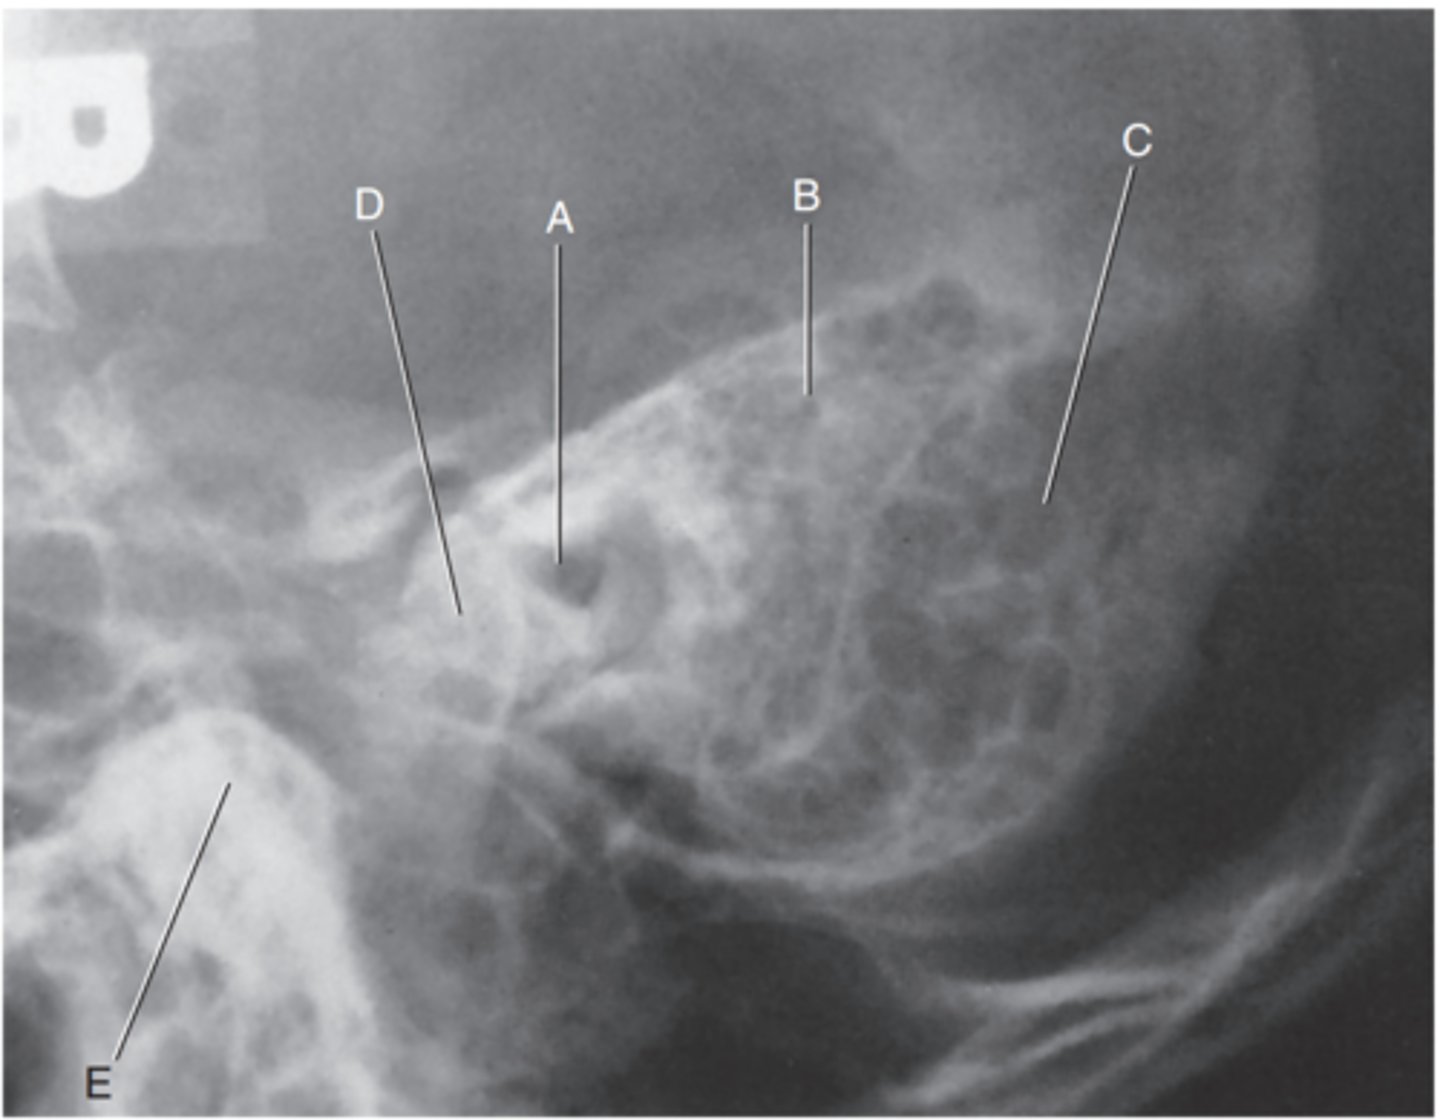

Petrous ridge

Label A

Bony (osseous) labyrinth (semicircular canals)

Label B

EAM

Label C

Region of internal acoustic canal

Label D